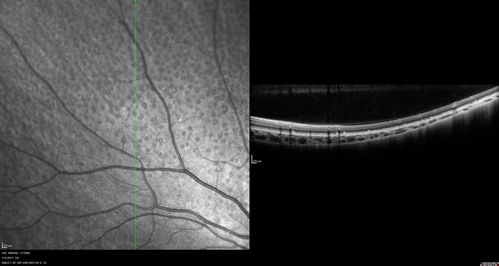

Fundus Albipunctatus

12 year old female with normal vision. She has 4 siblings all of whom have either white spots or spots on IR. Genetic testing by parents was deferred.